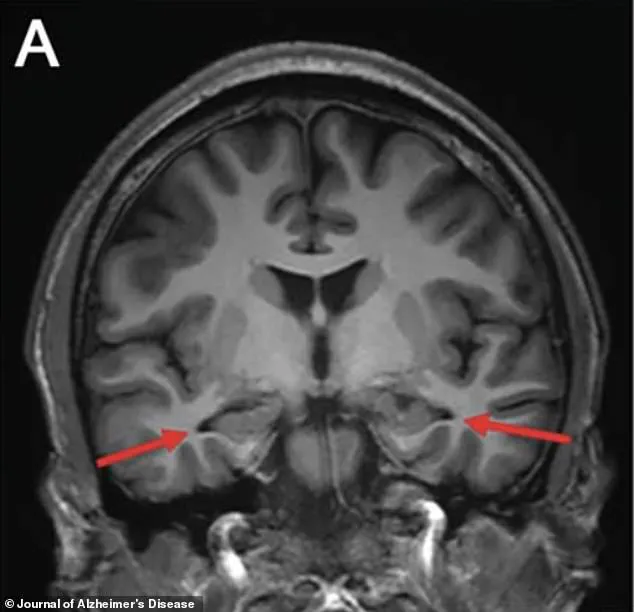

An MRI of the brain revealed a chilling revelation: the hippocampus, the region responsible for memory formation, was visibly shrinking.

Other scans confirmed reduced activity in the parietal and temporal cortices, areas critical for memory and cognitive processing.

The images, marked with arrows pointing to the affected regions, offered a stark visual representation of the brain's deterioration.

These findings were a red flag, suggesting a progressive and potentially irreversible condition.

In 2022, advanced brain scans revealed a chilling detail: significant shrinkage in the hippocampus, a region of the brain critical to memory formation and one of the first areas targeted by Alzheimer’s.